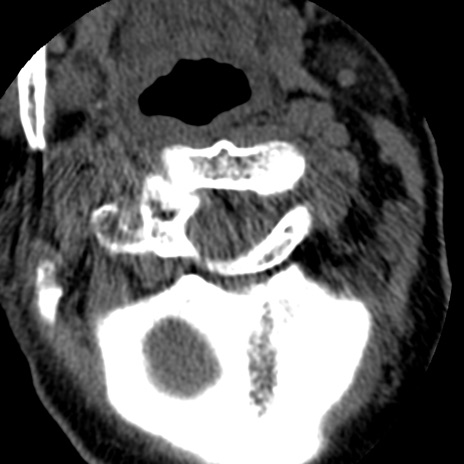

症例50 頚椎CT(横断像)

異常所見と診断は?

頚椎CT